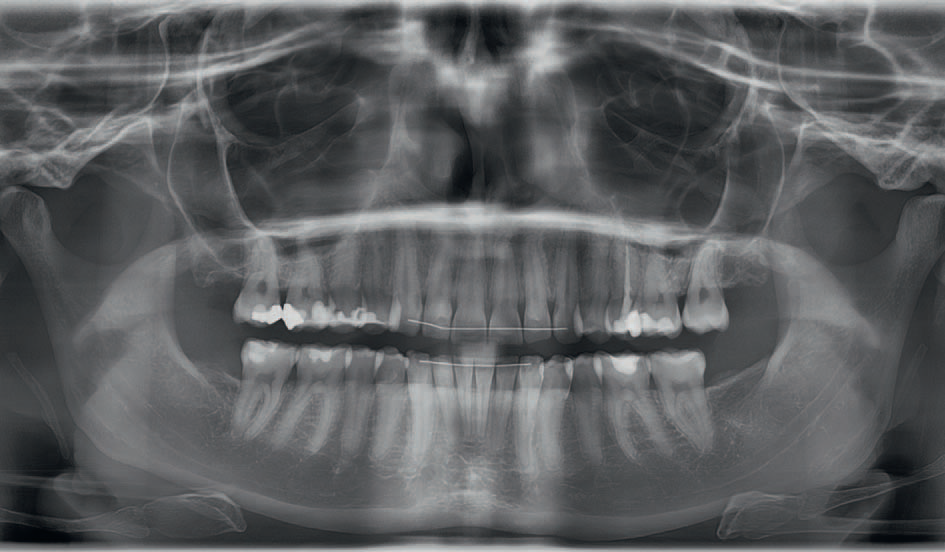

Streszczenie: Celem pracy jest prezentacja przypadku dorosłej pacjentki z klasą II grupą 2, leczonej techniką lingwalną w połączeniu z wysunięciem żuchwy. W pracy opisano wszystkie etapy terapii, dowodząc, że zastosowanie aparatu Herbsta i całkowicie indywidualnego aparatu językowego WIN umożliwia efektywne leczenie wady dotylnej z retruzją zębów siecznych.

Od momentu wprowadzenia aparatów językowych w latach 70. ubiegłego stulecia [1, 2] liczba pacjentów pragnących niewidocznego leczenia ortodontycznego stopniowo wzrasta. Przełomowe okazało się zaprojektowanie aparatów w pełni indywidualnych (CCLA) [3]. Ich ciągły rozwój doprowadził do powstania aparatów z zamkami WIN, które zapewniają większą precyzję, łatwiejsze klejenie i aktywację, dzięki czemu można je stosować zarówno u pacjentów dorosłych, jak i dzieci [4]. Zakres leczonych wad zgryzu uległ znaczącemu rozszerzeniu. Na początku ortodoncji językowej ograniczano się do leczenia nieprawidłowości zębowych w łuku dolnym [1], dziś leczone są wszystkie wady zgryzu, łącznie z przypadkami ekstrakcyjnymi [5] i operacyjnymi [6]. Zaczęto również łączyć aparaty językowe z innymi elementami wspomagającymi jak: Headgear, miniśruby czy aparat Herbsta [7, 8]. [...]